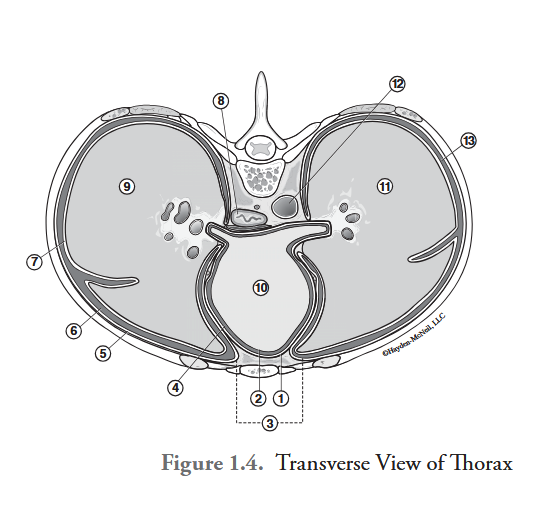

What is labeled #1?

parietal pericardium

What is labeled #2?

visceral pericardium (epicardium)

What is labeled #3?

mediastinum

What is labeled #4?

pericardial cavity

What is labeled #5?

parietal pleura

What is labeled #6?

right pleural cavity

What is labeled #7?

visceral pleura

What is labeled #8?

esophagus

What is labeled #9?

right lung

What is labeled #10?

heart

What is labeled #11?

left lung

What is labeled #12?

descending aorta

What is labeled #13?

left pleural cavity